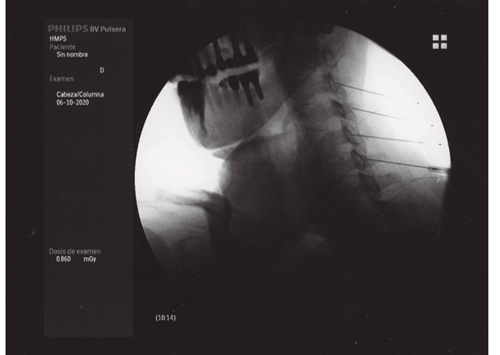

Aunque la articulación de la cadera se afecta con menos frecuencia que la rodilla, también parece despertar menos curiosidad e interés de las publicaciones, pues son muchas menos que sobre la rodilla. La inervación de la cadera está bien estudiada (24,25,26). El resumen de todas estas publicaciones es que la cápsula articular de la cadera recibe inervación en su cara anterior de los nervios femoral (cuadrante supero externo) y obturador en el cuadrante ínfero interno. Se ha demostrado que la denervación de la cápsula articular en la cara anterior produce un alivio del dolor en los pacientes con coxartrosis avanzada que no pueden ser tratados con una prótesis total debido a diferentes factores (edad avanzada, comorbilidades o riesgo quirúrgico elevado). Esquematizando mucho la inervación de la cara anterior de la cadera resumiría en que las ramas articulares del femoral se localizan en la parte superior y externa del cotilo femoral, mientras que las ramas articulares del obturador se localizan en la parte inferior sobre la rama descendente del isquión en su unión con el borde inferior del cotilo. La primera publicación describiendo una técnica de denervación con radiofrecuencia de la cara anterior de la cápsula articular de la cadera se produce en 2001 (27), en el que Kawaguchi describió una técnica con una aguja colocada en el borde anterolateral del cotilo para lesionar las ramas del nervio femoral, y otra en la parte inferior en la unión entre la parte externa de la rama pubiana y la descendente del isquión para lesionar las ramas del obturador mediante radiofrecuencia térmica; obtiene buenos resultados en disminuir el dolor en pacientes con coxartrosis. En los años siguientes se siguen publicando trabajos con un abordaje similar al de Kawaguchi, con control radiológico o con control ecográfico (28,29,30), así como algunas series de casos con radiofrecuencia pulsada (31). En 2018 se publicó una revisión de la evidencia que concluye que ninguno de los trabajos publicados es un RCT y que es necesaria su realización con una metodología de alta calidad para poder valorar el papel de estas técnicas. En 2008 (32)una publicación hace una valoración de la anatomía radiológica del nervio obturador, analizando la dificultad que tiene lesionar todas las posibles variaciones anatómicas de las ramas articulares del obturador con una sola aguja, además de analizar la dificultad que presenta el abordaje anterior de estas ramas debido a la presencia del paquete vásculo-nervioso femoral, que se interpone en el trayecto de las agujas, recomendando introducirlas de manera anterolateral con un ángulo de al menos 70° con el plano vertical. Termina proponiendo la realización de tres lesiones para asegurar la neurotomía de la mayoría de las ramas articulares. Basándonos en este artículo, desarrollamos una variación de la técnica de Kawaguchi en la que utilizamos tres agujas en la zona superoexterna del cotilo, y otras tres agujas en la parte inferior en la rama ascendente del isquión, introducidas de manera lateral con un ángulo al menos de 70° respecto al plano vertical, y realizando una lesión en empalizada con radiofrecuencia térmica bipolar entre cada dos agujas (Figura 3), obteniendo buenos resultados en más del 60 % de los pacientes tratados, que fue objeto de una comunicación a un congreso de la SED. Estas técnicas tienen que ser validadas en cuanto a su reproducibilidad y resultados, careciendo en estos momentos de evidencia, y de la estandarización de las referencias anatómicas y radiológicas para su realización (33).

Fig. 3.

La neurotomía por radiofrecuencia de las ramas articulares de los nervios femoral y obturador es una técnica no estandarizada, cuyas referencias anatómicas y radiológicas están todavía sin establecer y que precisarán de la realización de RCT de calidad para poder conseguir datos de evidencia sobre su utilidad. En mi opinión la realización de lesiones en empalizada con dos o tres agujas puede mejorar la posibilidad de lesionar la mayoría de las ramas sensoriales que, debido a las variaciones anatómicas, pueden ser difíciles de lesionar con una sola aguja. El principal peligro y complicación de esta técnica es la aparición de hematomas por punción accidental de la arteria femoral, si el abordaje se hace de manera vertical. La técnica se puede realizar con control radiológico o ecográfico, ofreciendo la ecografía la ventaja de poder visualizar el paquete vasculonervioso femoral.